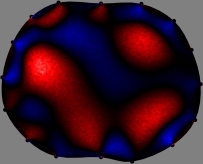

Figs. 3 and 4 compare the performance of the proposed FER method in (20) with the standard regularized least-squares method ((19) when \mathcal{R} is the identity matrix). The regularization parameter of the standard method was heuristically chosen for its best performance, and the parameter of the FER method was set to be one of three different values λ=0.05,0.2,𝜆0.050.2\lambda=0.05,0.2,\infty. The injection current was 1 mARMSRMS{}_{\tiny{\mbox{RMS}}} at 100 kHz, and the frame rate was 9 frames per second. The reference frame at t0subscript𝑡0t_{0} was obtained from the maximum expiration state. The measured data, 𝐕˙(tm)˙𝐕subscript𝑡𝑚\dot{\mathbf{V}}(t_{m}), represent the voltage differences between each time tmsubscript𝑡𝑚t_{m} and t0subscript𝑡0t_{0}. The blue regions, which denote where conductivity decreased by inhaled air, increased during inspiration and decreased during expiration. The FER method with λ=𝜆\lambda=\infty was clearly more robust than the standard method that produced more artifacts originated from the inversion process.

Figure 4: The reconstructed images of the conductivity change of the subject B by the standard regularized least square method and the proposed fidelity-embedded regularization (FER) method for three difference values λ=0.05,0.2,𝜆0.050.2\lambda=0.05,0.2,\infty. Here, the time step is 0.55 seconds (tm+5tm0.55subscript𝑡𝑚5subscript𝑡𝑚0.55t_{m+5}-t_{m}\approx 0.55).